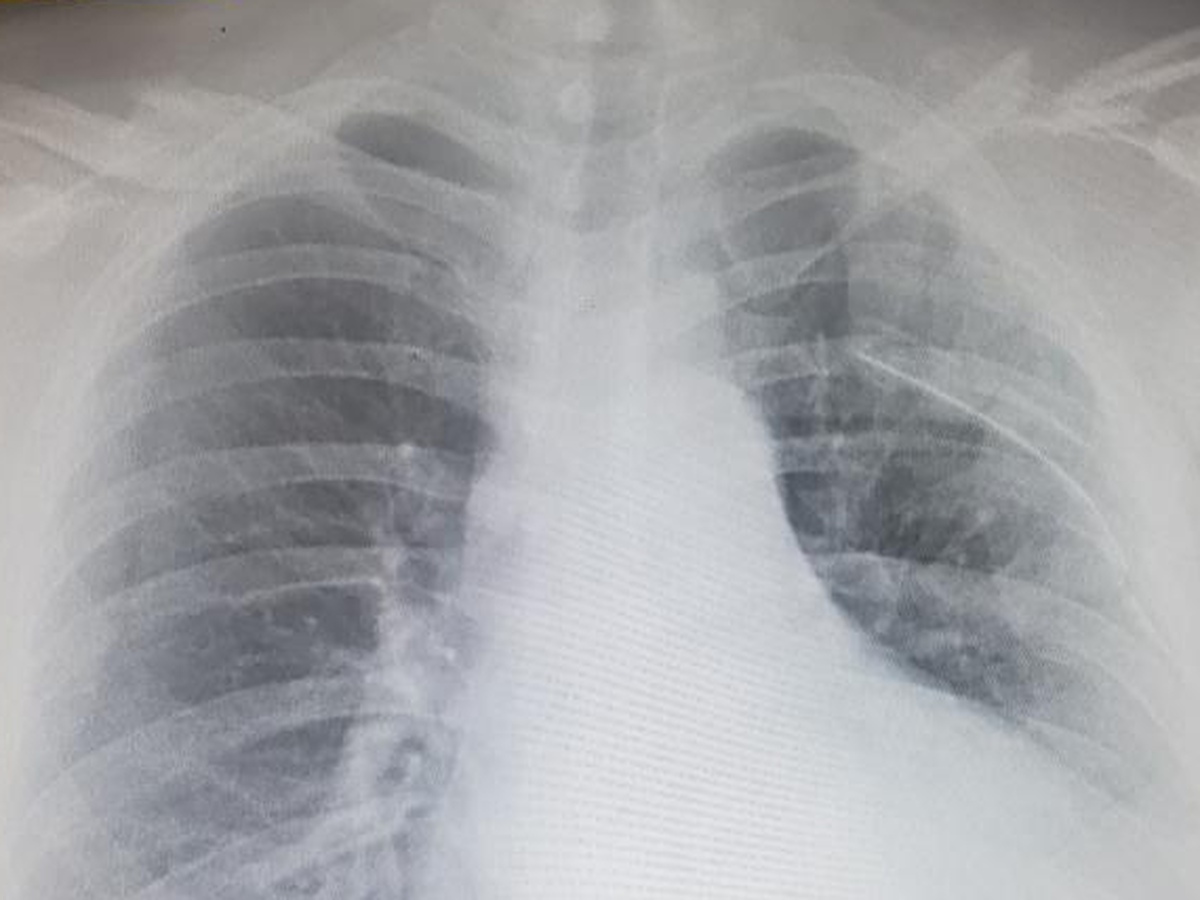

As many of you know, Tug recently ended up in the hospital with a punctured lung, broken ribs, and a broken collar bone. We are asking anybody and everybody to help pay his medical bills or at least help cover bills while he is out of work. Anything helps!